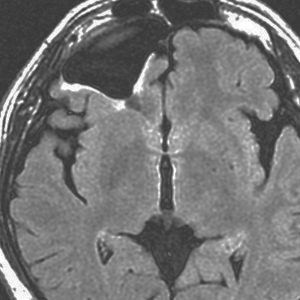

右前頭葉の乏突起膠腫グレード2です。46グレイとテモゾロマイドの治療で落ち着いていました。右側は初回治療後12年目の再発です。

とても限局性の再発でしたので,開頭手術で全摘出 supratotal resection しました。

オリゴには,浸潤性ではなくて,表面的で限局性の再発も多いです。でも多少は浸潤しているので,再度の再発の可能性は残ります。